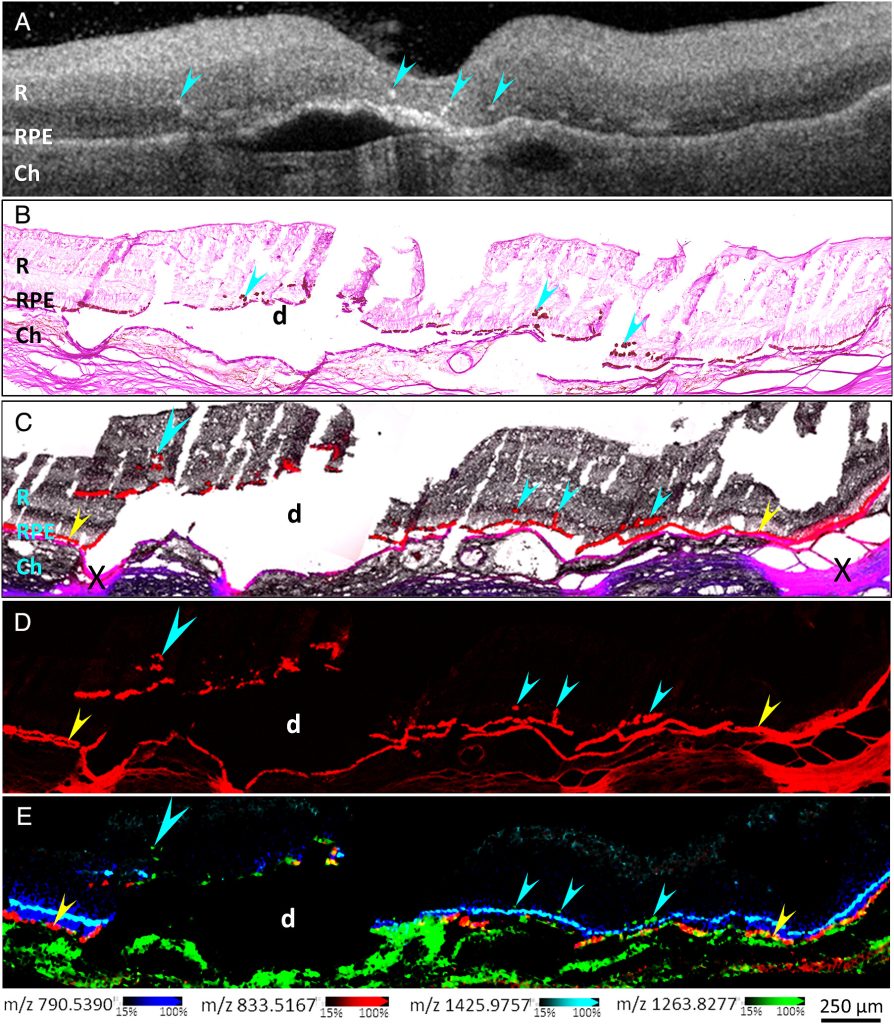

One contributing factor in diagnosing AMD is the presence of “hyperreflective foci” in the retina—the light-sensing part of the eye—using a technique called optical coherence tomography. The foci are small, discrete lesions in the retina that have high reflectivity and can be reliably tracked with OCT, serving as biomarkers for the disease.

We set out to dig into the molecular and cellular nature of hyperreflective foci in OCT scans of retinas with age-related macular degeneration. We believe that retinal pigment epithelium or RPE cells can undergo changes and migrate from their normal positions in the RPE monolayer and become the source of clinically visible hyperreflective foci. There are other potential sources of hyperreflectance in the retina, but our work aimed to assess the role of RPE cells as a key source of this biomarker signal.

We used near single-cell resolution imaging mass spectrometry, or IMS, to determine the molecular constituents of migrating RPE cells in human donor retinas. IMS was pioneered at Vanderbilt at the cutting-edge facilities within the Mass Spectrometry Research Center and it facilitated our analysis.

We found that the molecular signatures of hyperreflective cells in AMD eyes are consistent with ectopic (migrating) RPE cells. As RPE cells migrate into the inner retina, changes in their molecular composition were consistent with transdifferentiation, a process that morphs the normally static epithelial cells into mesenchymal cells, which are characterized by migratory and invasive properties. We also found that the ectopic RPE cells both gain some functions they didn’t have in the RPE layer and lose some functions they had before, which we believe is caused by altered lipid metabolism in the ectopic cells. We believe that this change in lipid metabolism drives migration and the creation of the hyperreflective foci and leads to the progression of AMD.

Right now, we believe that this research confirms that some hyperreflective foci observed in OCT scans occur due to transdifferentiating RPE cells and that lipid metabolism is altered in these cells.